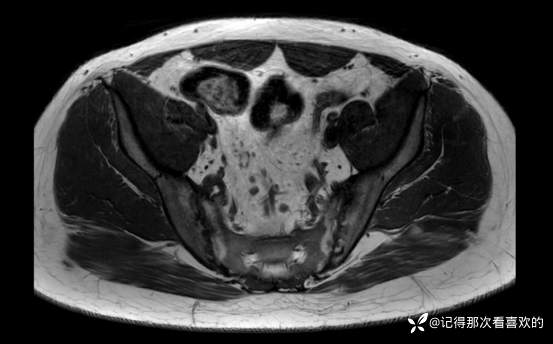

06-05 骶髂关节MRI平扫:1、双侧骶髂关节改变,符合为强直性脊柱炎所致。请结合临床实验室检查结果。2、左髋关节少量积液。请结合临床及其他检查,随诊。